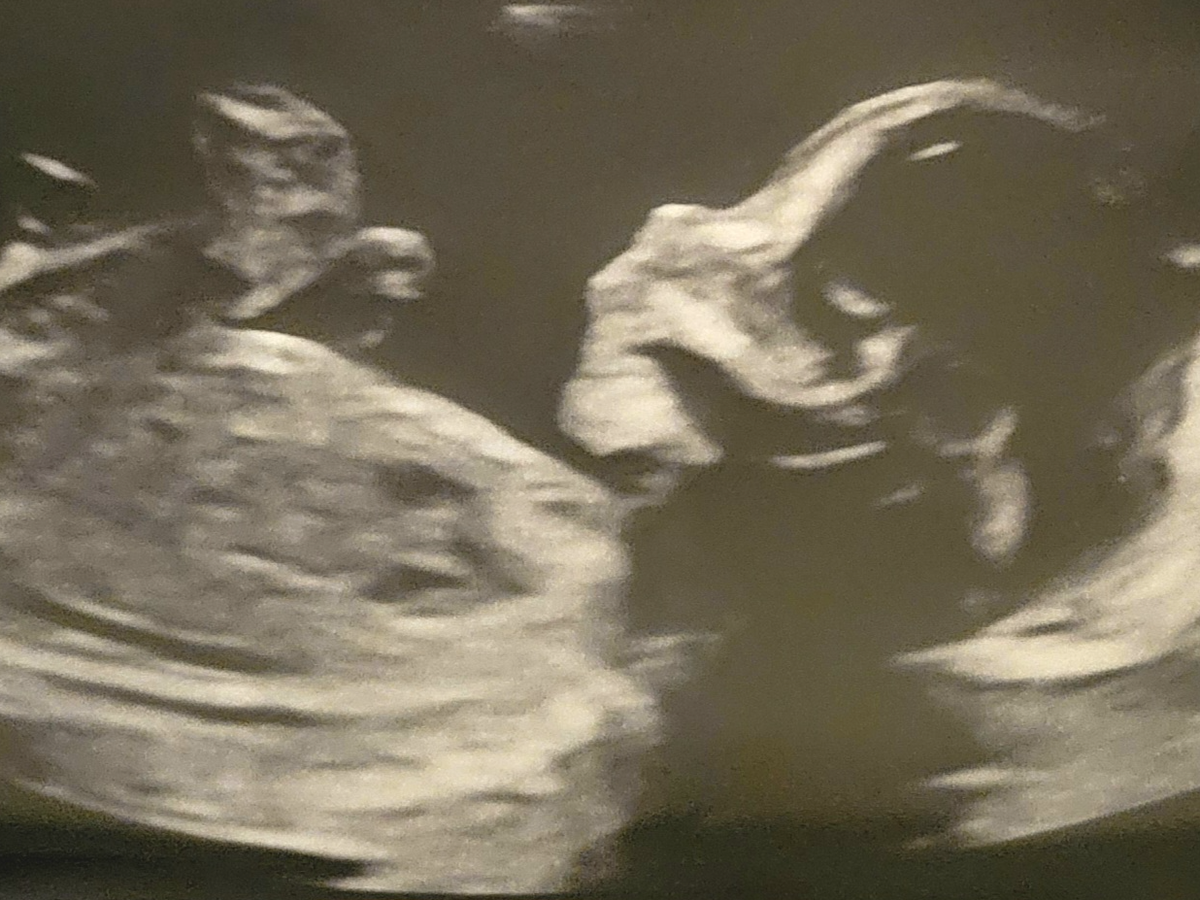

Hello our names are Chris and Sabrina we are parents of two incredible boys. With much pain in our hearts we will have another baby boy that will soon be born into heaven. Our pregnancy journey turned into unexpected shocking moments when we did the anatomy scan and were told there were abnormal findings. Immediately we were referred to the high risk OB for another ultrasound. With much hope in our hearts we prayed that the findings were not true and possibly a mistake. Anxiously waiting for the doctor to talk to us our hopes were shattered when it was fully confirmed.

Our baby was diagnosed having a severe condition with fluids in the spine upto the brain. We were devastated with the news. When the doctor told us what our options were we never thought we would be in this terrible situation.

Due to the fluids severly impacting the brain it caused further abnormal findings. Our hearts broken and in despair, we are giving our baby grace and salvation into the kingdom of heaven. With much sadness and grief we remind ourselves of our two little boys who need us, to give us strength, and move forward with courage.